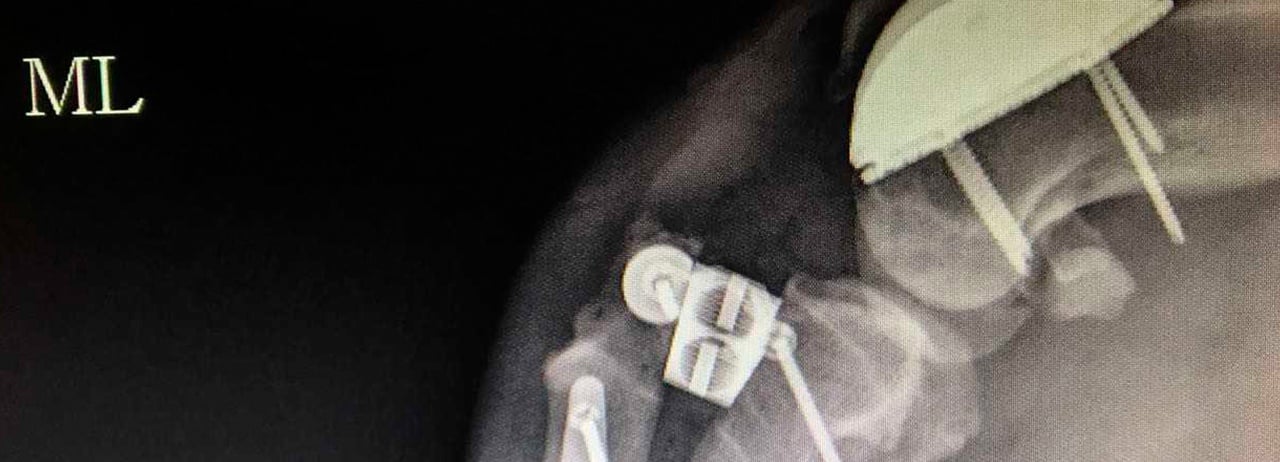

El procedimiento fue realizar el reemplazo del surco troclear PGR (patellar group replacement). “Se reemplazó el surco degenerado por una prótesis de titanio extra pulido o ultra pulido. Esta prótesis lo que busca es tener una superficie articular sumamente lisa para evitar que haya un roce inadecuado entre la rótula y la superficie articular degenerada”, indicó el especialista en ortopedia.

Beremiz Sánchez, encontró que Chavy presentaba luxación patelar grado IV -es decir que su rótula salió del surco  de la rodilla-, y como consecuencia de ello sufrió desalineación del músculo cuadricep desarrollando a lo largo del tiempo una enfermedad degenerativa severa en su rodilla.

Además presentaba, ruptura del ligamento cruzado craneal, condición muy común en caso de luxación patelar y que predispuso a una mayor inestabilidad e inflamación articular.

El especialista detalló que el procedimiento a efectuarse era colocar un surco protésico para mejorar su condición biomecánica y contrarestar el dolor.